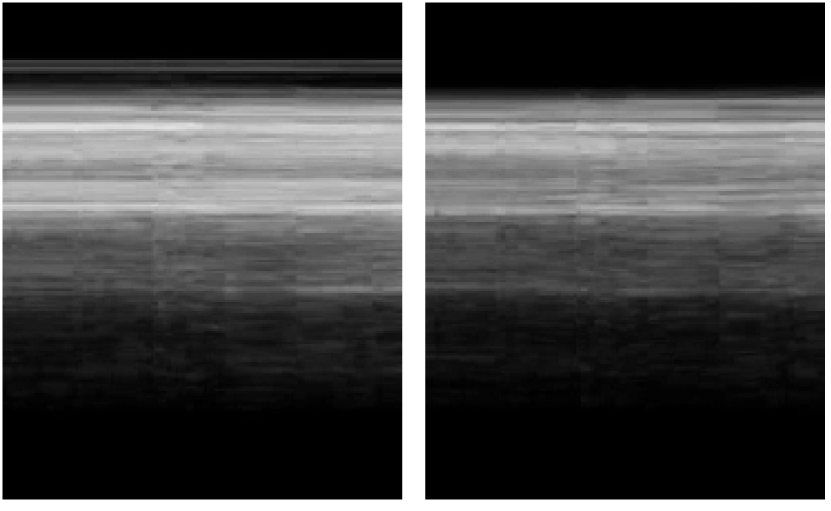

As outlined in Sec. 3.1.1, the brightest 50%percent5050\% of the M-mode images within the bounds of the pleural line are utilized for pretraining. We consider any such M-mode images from the same video to be a positive pair. Qualitatively, different M-mode images produced from the same B-mode video appear very similar. Crucially, they would have the same lung sliding label, fulfilling the alignment condition outlined in [4]. Fig. 3 displays examples of positive pairs of M-modes. We fix the pairwise relationship to focus on evaluating data augmentation transformations and the effects of pretraining under different settings, relegating an ablation study for the M-mode pairwise relationship to future work.

Refer to caption

(a) Lung sliding, seashore sign.

(b) Lung sliding, seashore sign.

(c) Absent lung sliding, barcode sign.

(d) Absent lung sliding, barcode sign

Figure 3: Examples of M-mode images satisfying the pairwise relationship of belonging to the same original B-mode video and intersecting the pleural line.